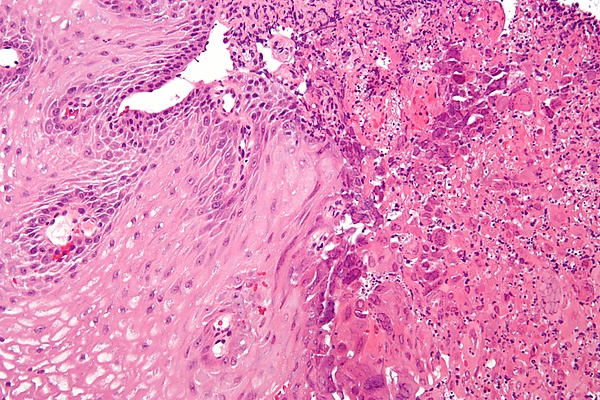

Кандида может входить в состав нормальной микрофлоры полости рта. Из-за нарушения клеточного иммунитета эпителиальный слой пищевода становится восприимчивым к инфекции и колонизации кандидой. Кандида размножается и прикрепляется к слизистой оболочке пищевода, образуя бело-жёлтые налёты. Может быть поражён любой отдел пищевода или весь пищевод на протяжении[3].

Диагностика КП проводится с помощью эзофагогастродуоденоскопии (ЭГДС). Визуализация белых налётов или экссудатов на слизистой оболочке пищевода подтверждает диагноз. Налёт и экссудаты плотно прикреплены к слизистой и не смываются при орошении водой. Также могут наблюдаться повреждения слизистой или изъязвления. Для гистологического подтверждения диагноза могут быть взяты биоптаты или соскобы с налётов[3].